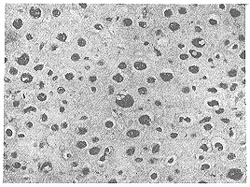

NF-κBp65亚单位免疫组化阳性产物呈棕褐色细颗粒状,主要定位于肿瘤细胞胞浆,见图1。80例骨肉瘤中48例NF-κBp65阳性,阳性率为60%。在10例骨纤维结构不良和5例骨母细胞瘤中NF-κBp65免疫组化结果阴性,边缘性反应骨和外伤性骨痂组织未见着色。

图1 软骨母细胞型骨肉瘤NF-κB p65蛋白免疫组化染色,阳性反应主要定位于肿瘤细胞胞浆 (LSAB×200)

Fig 1 Immunohistochemical staining of NF-κB p65 subunit in osteosarcoma of chondroblastic type, the positive product was mainly localized in the cytoplasm of tumor cell (LSAB×200)